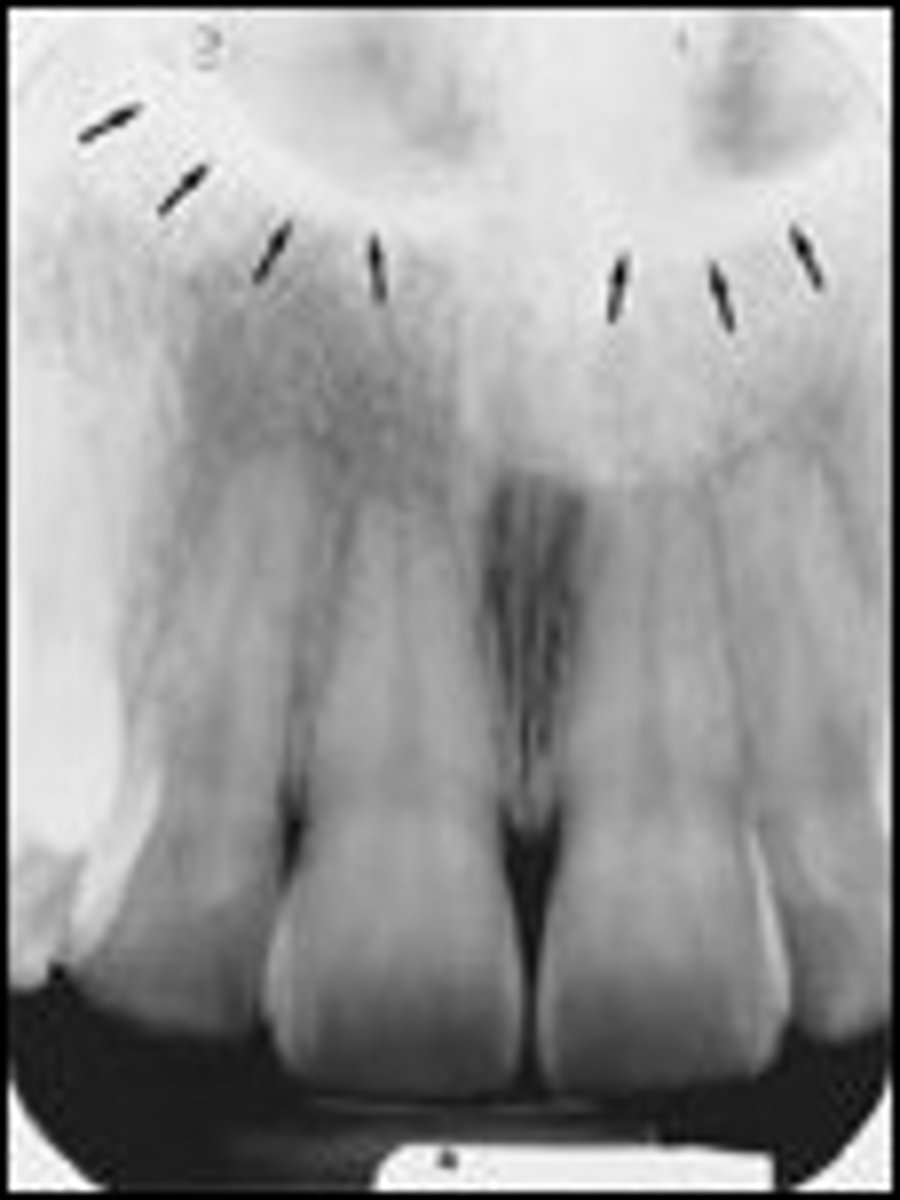

Superior foramina of the incisive canal

What is the radiolucent structure seen here?